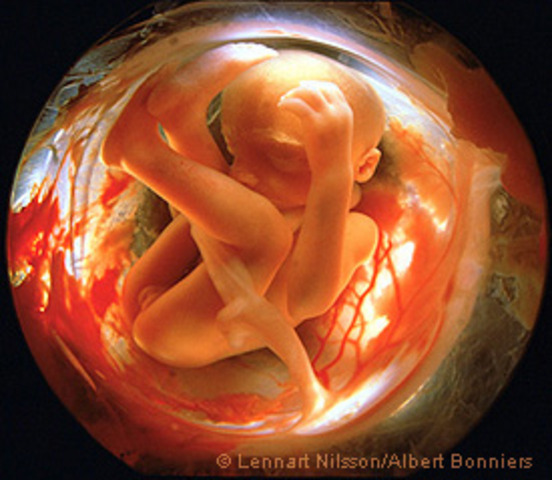

• DESARROLLO FETAL: SEMANA 30 A 38

VIDEO

Ya se encuentran en la posición adecuada para el momento del parto, con la cabeza hacia abajo y los glúteos hacia arriba. Su cráneo todavía no está totalmente sólido, ya que necesita pasar por el canal de parto. Desliza su pulgar dentro de su boca y practica el reflejo de succión.